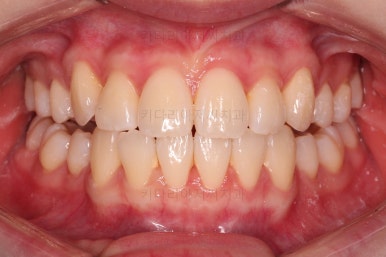

마찬가지로 초진 시 입안의 모습인데요.

전반적으로 약간 삐뚤지만 특히 윗니 앞니가 삐뚤고요.

송곳니는 덧니처럼 튀어나와 보이네요.

그리고 전반적으로 치아가 앞쪽으로 경사되어 있어서 앞니는 뻗친 느낌이 있네요.